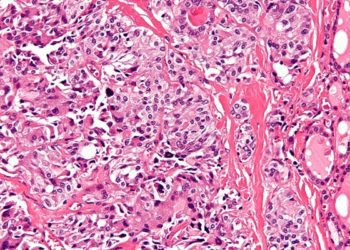

Study Rundown: There is a high incidence of thyroid nodules in the general population, but only a small percentage of these are malignant. Furthermore, many thyroid neoplasms may never become clinically significant. This study identifies 3 high risk ultrasonographic features of malignant thyroid nodules by comparing thyroid ultrasounds of known malignant nodules with those of non-cancerous nodules. By using the California Cancer Registry to identify cases of thyroid cancer within the study population of all people who underwent thyroid ultrasound at UCSF during the study period, this study avoided the ascertainment bias of prior studies, which looked only at nodules which underwent biopsy.

The study found that only 3 ultrasonographic findings conveyed an increased risk of malignancy including: microcalcifications, size >2cm and entirely solid composition. Other characteristics did not signify an increased risk of cancer. Based on their model, they suggest that reasonable criteria for biopsy would be the presence of microcalcifications or 2 or more of the criteria, which would yield a false negative rate of only 0.5% and would substantially reduce the number of biopsies performed. This study is limited by the fact that it is based on data from only one institution, and there was a minimum of only 2 years of follow-up, so clinically significant cancers could have developed after the study period, and would not be captured by this analysis.

In-Depth [retrospective case-control study]: This study included a total of 11,618 examinations performed on 8,806 patients, of whom 105 were subsequently diagnosed with cancer of the thyroid. It was found that the presence of microcalcifications in a thyroid nodule conveyed the highest risk of malignancy and were present in 38.2 % of cancerous nodules as compared to 5.4% of benign nodules (OR, 8.1; 95% CI, 3.8-17.3; P<.001). Size >2cm was also associated with an increased risk of malignancy (OR, 3.6; 95% CI, 1.7-7.6; P=.001), as was an entirely solid composition (OR, 4.0; 95% CI, 1.7-9.2; P=.001). They found that the presence of any one of these characteristics was 88% sensitive for malignancy, but was non-specific and carried a risk of cancer of only 1.8% (95% CI, 0.015-0.022). The presence of microcalcifications alone conveyed an 8.2% (95% CI, 0.059-0.110) increased risk of cancer, while the presence of any 2 features had a 6.2% (95% CI, 0.047-0.080) increased risk. The number needed to biopsy in order to diagnose cancer was 12 (95% CI, 9-17) for microcalcifications, 16 (95% CI, 13-21) for any 2 features, as compared to 56 (95% CI, 45-67) for any single feature alone.